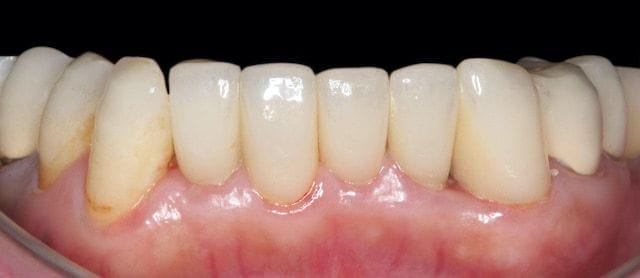

圖示:透過三顆陶瓷貼片與二顆全瓷冠,並選擇自然齒色完成微矯正

最後我們用三顆全瓷貼片和兩顆全瓷牙冠修復,選擇自然的齒色,得到滿意的結果。